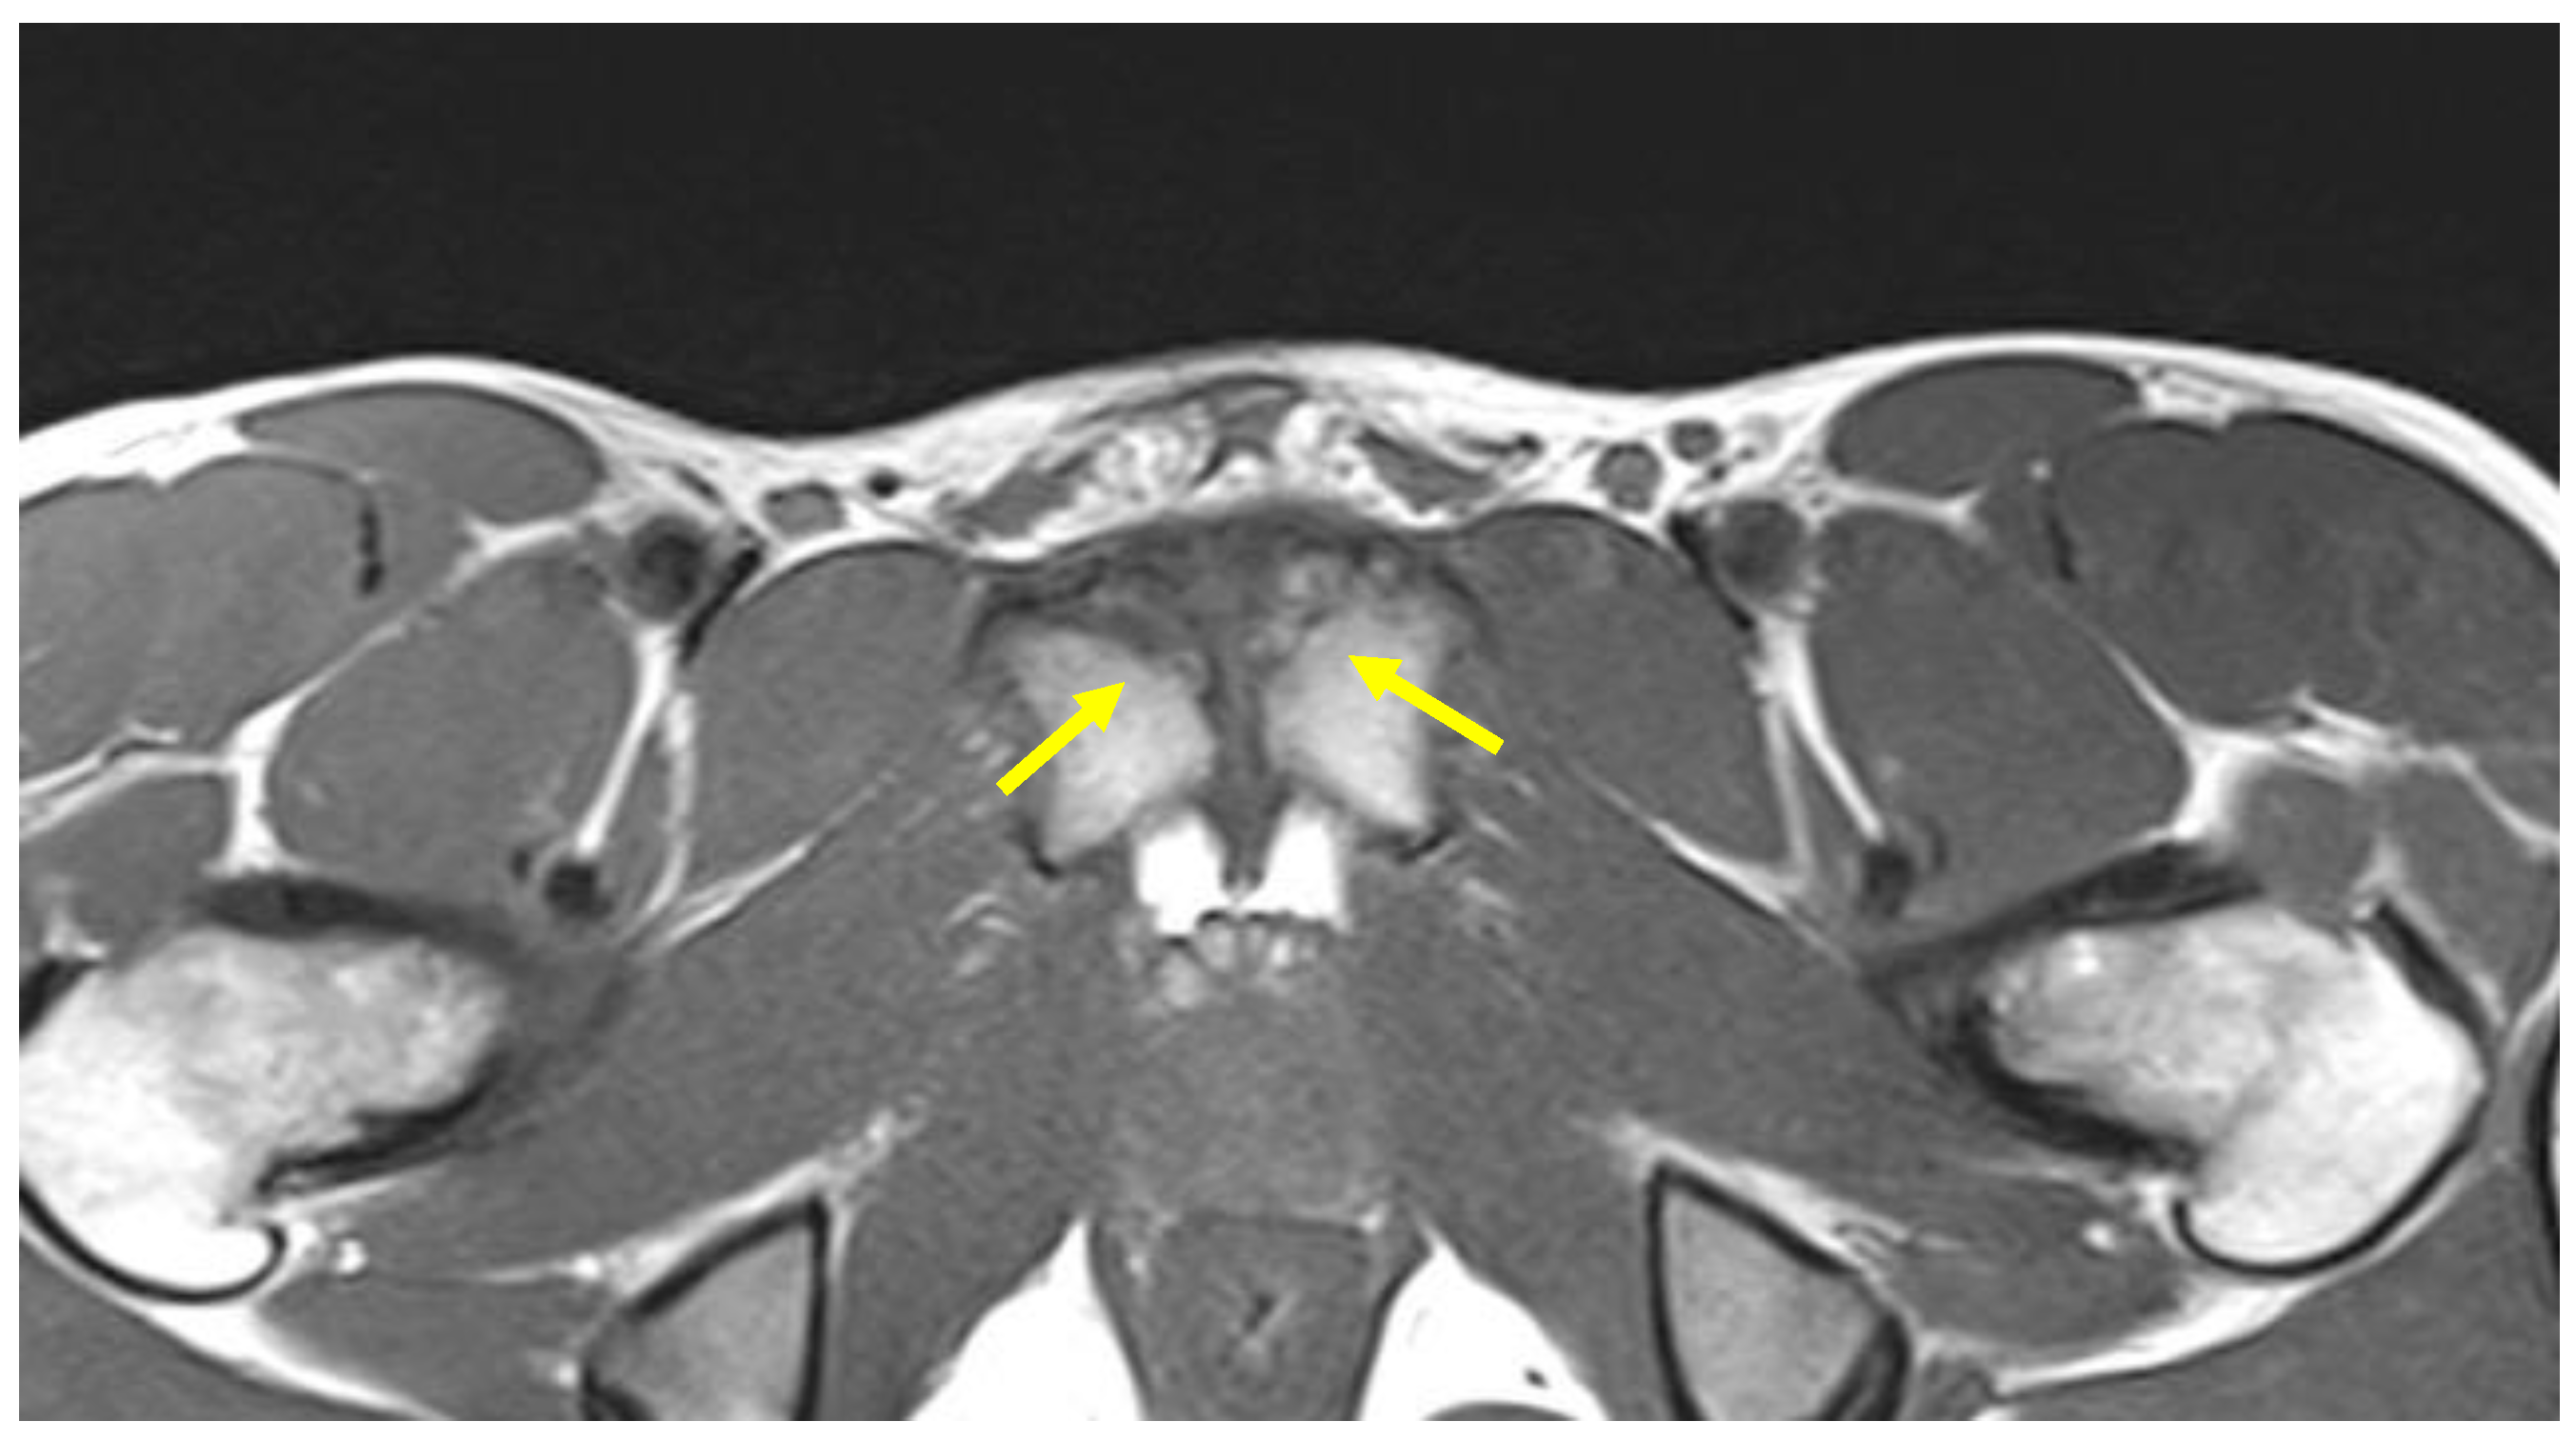

| Secondary inferior cleft sign | Coronal STIR. Axial oblique PD FS | High signal intensity line extending laterally and inferiorly to the lower part of the symphysis, which appears to be in communication with the symphyseal joint space. |

| Secondary superior cleft sign | Coronal STIR. Axial oblique PD FS | High signal intensity line in fluid-sensitive sequences extending parallel to the inferior border of the superior pubic ramus shows connection with the symphyseal joint space. |